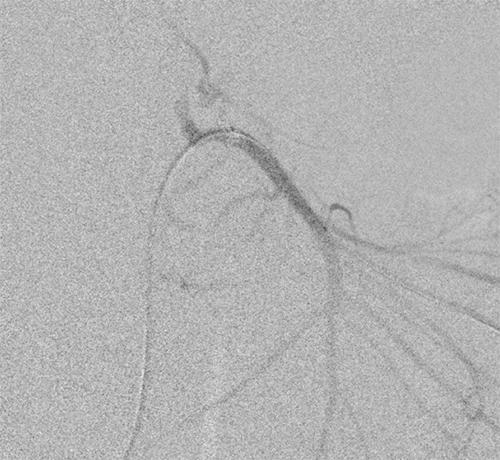

After REBOA inflation, the patient was able to maintain a mean arterial pressure >65mmHg, and her vasopressors were weaned off. She underwent an emergency visceral angiogram via a femoral approach from the contralateral side. Angiography revealed a ruptured pseudoaneurysm at a branch of the pancreaticoduodenal artery and a dislodgment of the previously placed gastroduodenal artery coils (Figure 2). Attempts at angioembolization were unsuccessful; therefore, an exploratory laparotomy was performed. Upon entry into the lesser sac, the REBOA was gradually released over a five-minute period as the surgical team controlled the bleeding by ligating arterial hemorrhage at the head of the pancreas. The REBOA was fully inflated for 58 minutes, and the REBOA catheter was removed after 110 minutes. The sheath was removed at the conclusion of the operation. The patient received ten PRBCs, seven FFP, two platelets, and a 450mL cell saver intraoperatively. She was initially managed with an open abdomen, and on postoperative day 2, the patient returned to the operating room for fascial closure. Postoperatively, the patient received one additional PRBC. There was very mild acute kidney injury with a peak creatinine of 1.1 (baseline 0.5) approximately 36 hours after REBOA placement. The remainder of her hospital course was uneventful.

Figure 2. Angiogram Imaging. Published With Permission

Image demonstrates bleeding off of gastroduodenal artery and in superior pancreaticoduodenal artery cascade.